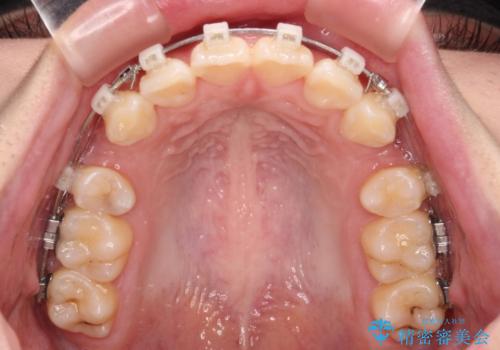

- 矯正装置

- クリアブラケット

口元の突出感の解消と、このままデコボコを解消するとさらに出っ歯傾向になってしまうことを考慮し、上下左右の小臼歯を抜歯しクリアブラケットにて矯正していくこととしました。

舌突出癖を改善するトレーニングを一生懸命やっていただいたおかげで2年以内に治療を終えることができました。